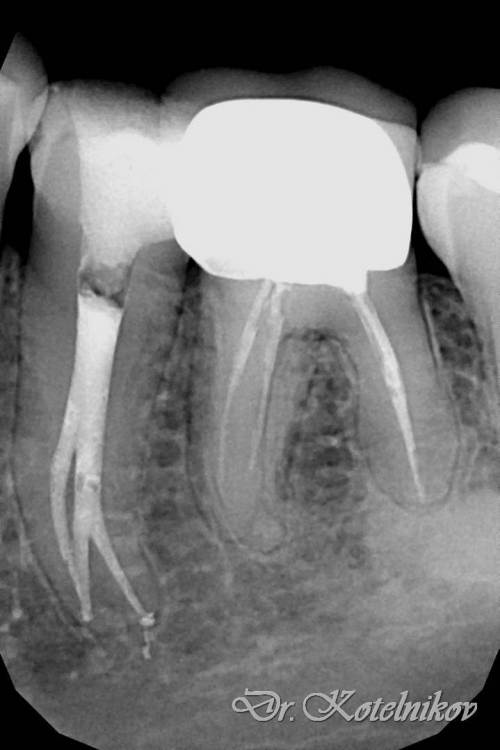

Ico Опубликовано 5 апреля, 2022 Автор Поделиться Опубликовано 5 апреля, 2022 Обострение хронического периодонтита зуб 36. После первичного эндо пропущен ДБ канал,зуб был восстановлен циркониевой вкв + циркон коронка.На пропИл до устья ушло 5 боров.Мед мех стандартный 40к+F1,паковка гибрид с Эйчем.2 визита по 2 и 1.5 часа. 3 1 Ссылка на комментарий